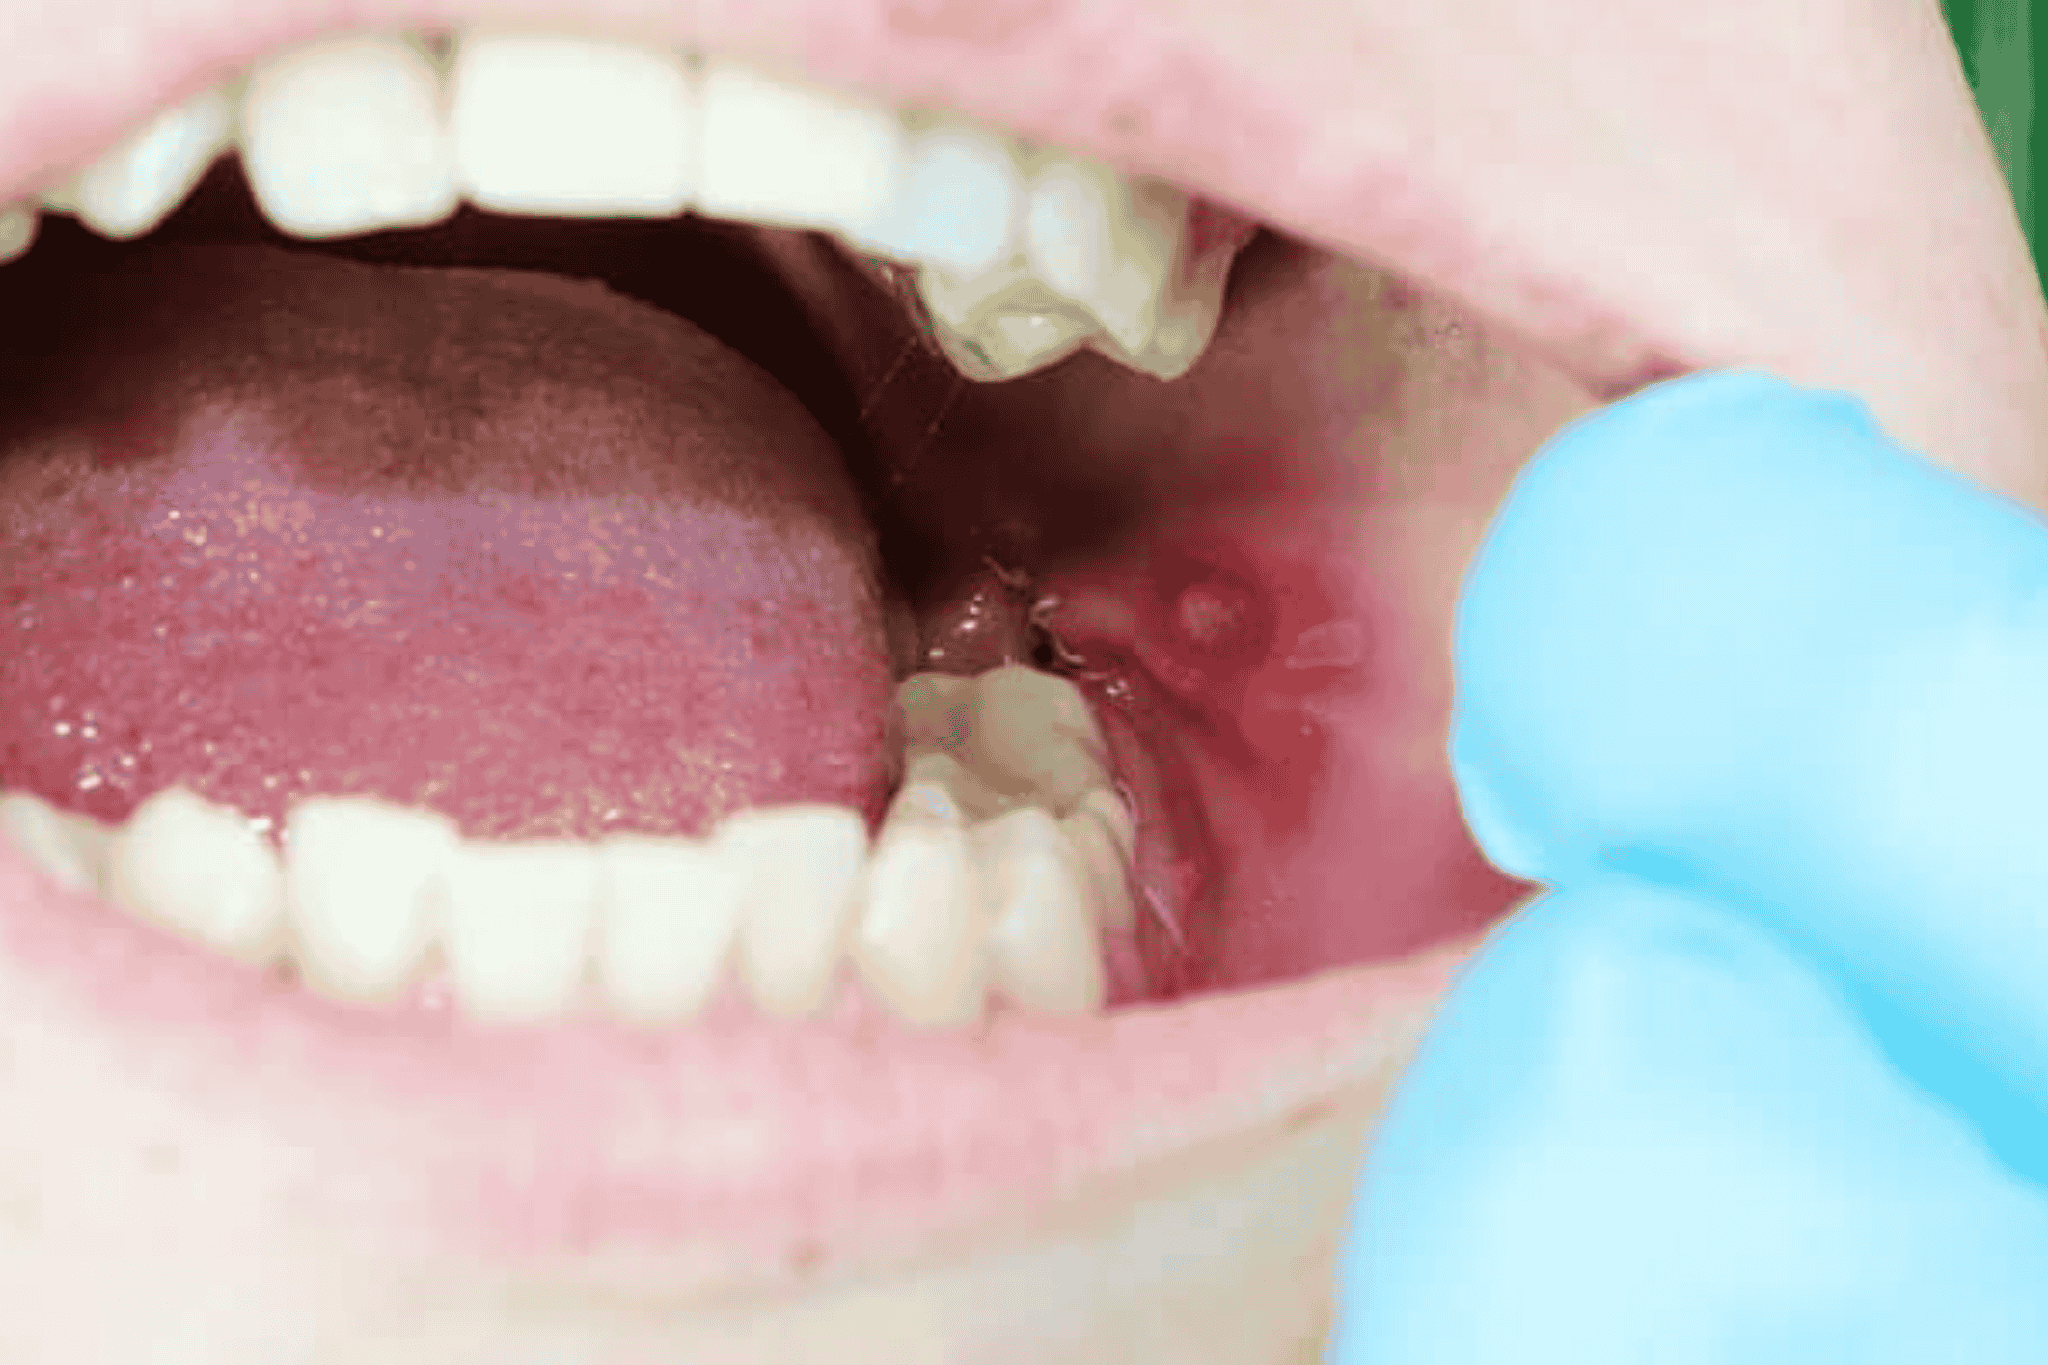

1. Afták - kicsi és kellemetlen

- Kis, kerek, fehéres sebek vörös szegéllyel.

- Fájdalmasak, főleg evés és beszéd közben, kísérő tünete lehet a láz.

- Leggyakrabban a nyelven, ínyen vagy ajkak belső részén fordulnak elő.

- 7-10 nap alatt maguktól is elmúlhatnak az afták, de ha 2 hétnél tovább “vendégeskednek”, vagy gyakori visszatérők, érdemes szakorvoshoz fordulni.